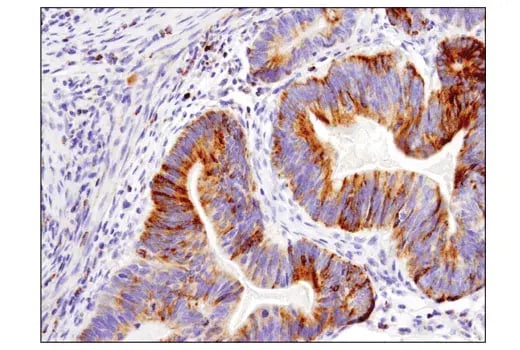

IHC analysis of paraffin-embedded human colon carcinoma using Cleaved-PARP (Asp214) (E2T4K) Mouse Monoclonal Antibody #32563.